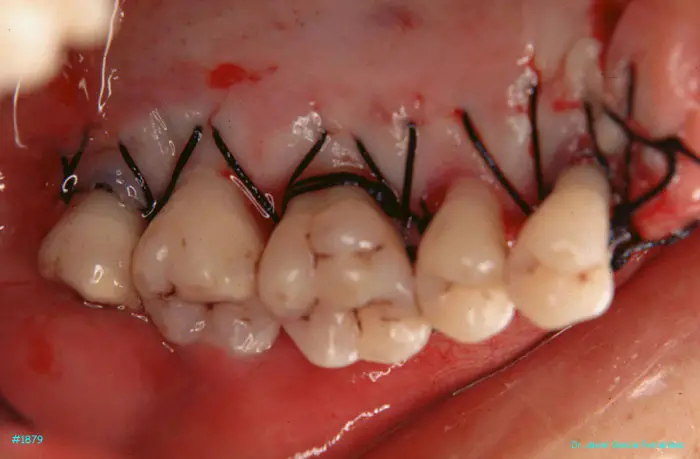

image 30